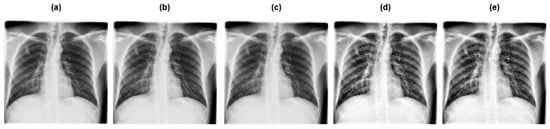

A Lightweight Hybrid Deep Learning Model for Tuberculosis Detection from Chest X-Rays

by Majdi Owda, Ahmad Abumihsan, Amani Yousef Owda and Mobarak Abumohsen

Diagnostics 2025, 15(24), 3216; https://doi.org/10.3390/diagnostics15243216 - 16 Dec 2025

Background/Objectives: Tuberculosis remains a significant global health problem, particularly in resource-limited environments. Its mortality and spread can be considerably decreased by early and precise detection via chest X-ray imaging. This study introduces a novel approach based on hybrid deep learning for Tuberculosis [...] Read more.

Background/Objectives: Tuberculosis remains a significant global health problem, particularly in resource-limited environments. Its mortality and spread can be considerably decreased by early and precise detection via chest X-ray imaging. This study introduces a novel approach based on hybrid deep learning for Tuberculosis detection from chest X-ray images. Methods: The introduced approach combines GhostNet, a lightweight convolutional neural network tuned for computational efficiency, and MobileViT, a transformer-based model that can capture both local spatial patterns and global contextual dependencies. Through such integration, the model attains a balanced trade-off between classification accuracy and computational efficiency. The architecture employs feature fusion, where spatial features from GhostNet and contextual representations from MobileViT are globally pooled and concatenated, which allows the model to learn discriminative and robust feature representations. Results: The suggested model was assessed on two publicly available chest X-ray datasets and contrasted against several cutting-edge convolutional neural network architectures. Findings showed that the introduced hybrid model surpasses individual baselines, attaining 99.52% accuracy on dataset 1 and 99.17% on dataset 2, while keeping low computational cost (7.73M parameters, 282.11M Floating Point Operations). Conclusions: These outcomes verify the efficacy of feature-level fusion between a convolutional neural network and transformer branches, allowing robust tuberculosis detection with low inference overhead. The model is ideal for clinical deployment and resource-constrained contexts due to its high accuracy and lightweight design. Full article